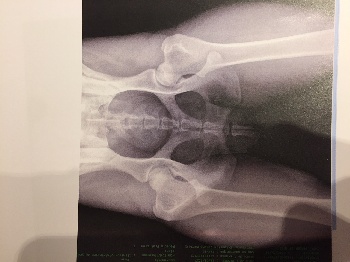

Radio des hanches Fanfan Azul de los Laureles

Les hanches sont parfaites A/A